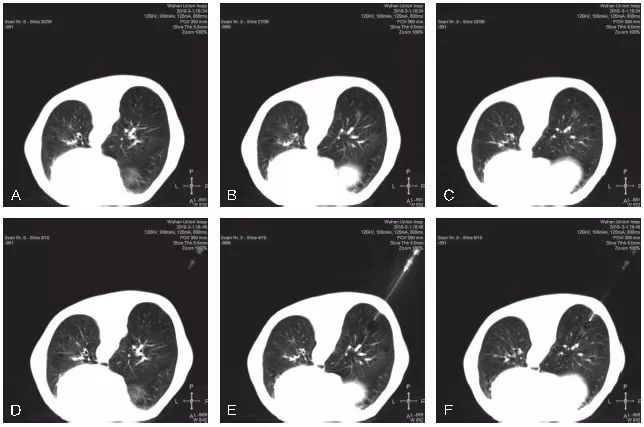

图5-3 展示了1例pGGO的CT引导下经皮穿刺活检

A~C. 显示患者左肺上叶前段胸膜下pGGO,选取仰卧位进行穿刺活检;D~F. 显示穿刺活检的实时CT影像;G~I. 显示活检完成后,拔除同轴穿刺针,再次进行CT扫描,未见明显气胸及肺内出血征象。病理结果示:(左肺)浸润性腺癌